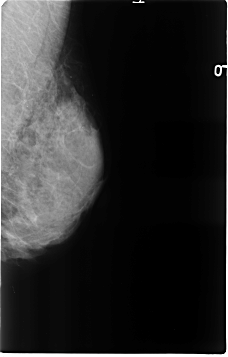

B_3120_1.LEFT_MLO

LEFT_MLO LINES 4632 PIXELS_PER_LINE 2960 BITS_PER_PIXEL 12 RESOLUTION 50 NON_OVERLAY